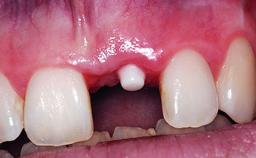

A 32-year-old female Caucasian patient with a compromised maxillary right central incisor was referred to us by a general dentist. Her chief complaints were discomfort and mobility of tooth 11 with unsatisfactory esthetics due to discoloration. The patient reported a previous trauma, some years earlier, as the origin of pathology on the afflicted tooth. Anamnesis was negative for any other dental or periodontal pathology in the remaining dentition. The patient did not take any medication and reported to be a light smoker (5–10 cigs/day). She had high esthetic expectations of her treatment. The extraoral examination revealed a high smile line with full exposure of her maxillary teeth and surrounding soft tissue in the area between the second premolars.

Placement Protocol Early or late implant placement

Bone Volume Deficient horizontally, requiring prior grafting